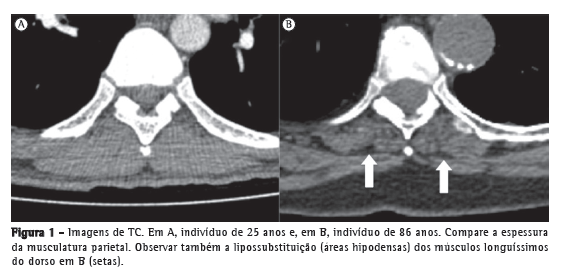

Um dos achados radiológicos mais comuns na parede torácica é a redução da espessura dos músculos parietais, que é bem demonstrada por TC, especialmente quando comparada com aquela de indivíduos mais jovens (Figura 1). Essa redução é uma das principais causas do aumento da transparência pulmonar em estudos radiográficos de tórax em idosos. Apesar de não haver estudos definindo a idade inicial para o encontro desse achado, sabe-se que isso decorre da perda de massa muscular associada ao processo fisiológico de envelhecimento, sendo mais evidente quanto maior for a idade do indivíduo.(4-10) Entretanto, não existem ainda critérios objetivos que permitam diagnosticar esse achado pelos métodos de imagem. Outro achado de ocorrência comum é a presença de calcificações da cartilagem costal, que se apresentam como pequenas ilhas de matéria óssea compacta e que podem ter aparência nodular, sendo confundidas, em alguns casos, com nódulos pulmonares solitários.(3)